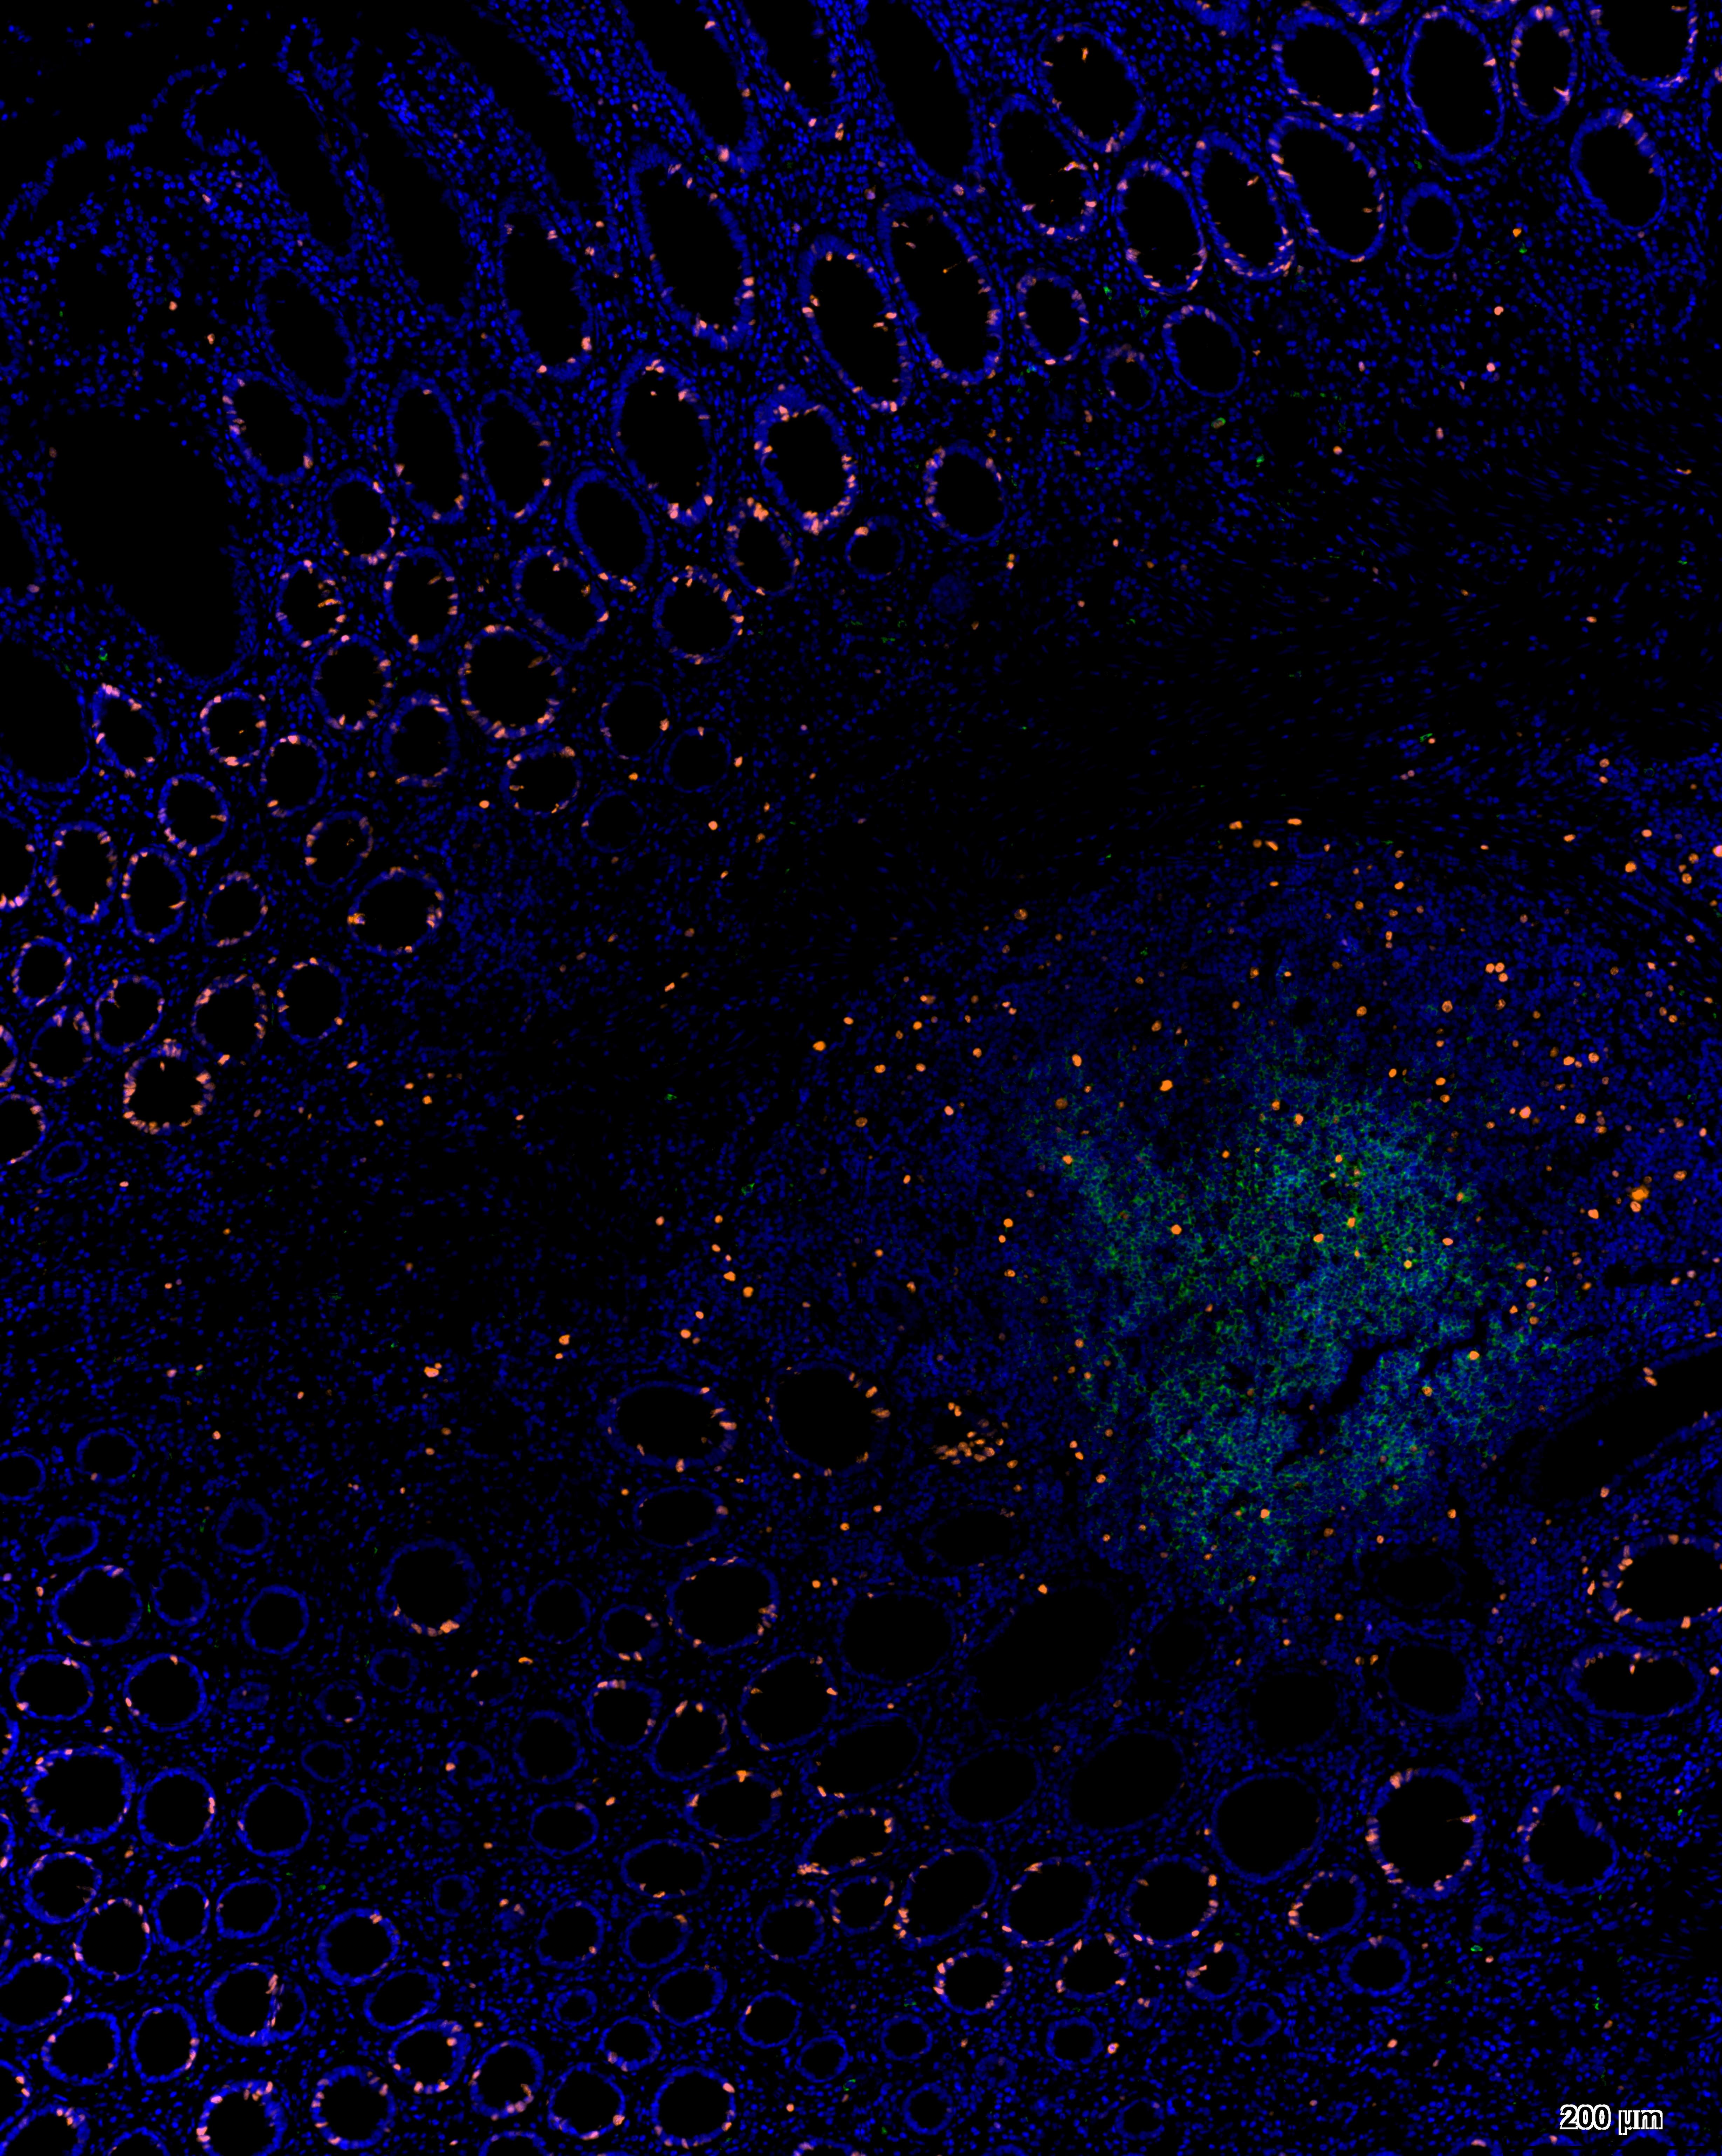

酪酰胺信号放大(TSA, Tyramide signal amplification)技术是一类利用辣根过氧化酶(HRP)对靶蛋白进行原位标记的酶学检测方法。其原理是利用酪胺(Tyramide)的过氧化物酶反应,酪胺荧光素底物在HRP和H202的作用下被活化,活化的荧光底物能与目标蛋白上的酪氨酸等残基共价结合,导致在抗原-抗体结合位点大量沉积荧光素,实现信号放大。通过热修复或者抗体洗脱液洗去前一轮非共价结合的抗体,而荧光素稳定结合在蛋白上,进行下一轮染色。直至所有抗体孵育结束,进行核染色,封片,扫描。

由于每次体系中都只有单一抗体孵育,因此无需担心抗体的交叉反应及一抗二抗种属匹配问题,摆脱了传统免疫荧光实验条件对抗体种属来源的限制和束缚。此试剂盒中的荧光染料可以单独或组合使用,能够实现单标、双标、三标以及更多重荧光放大/多重同源抗体荧光标记等功能。